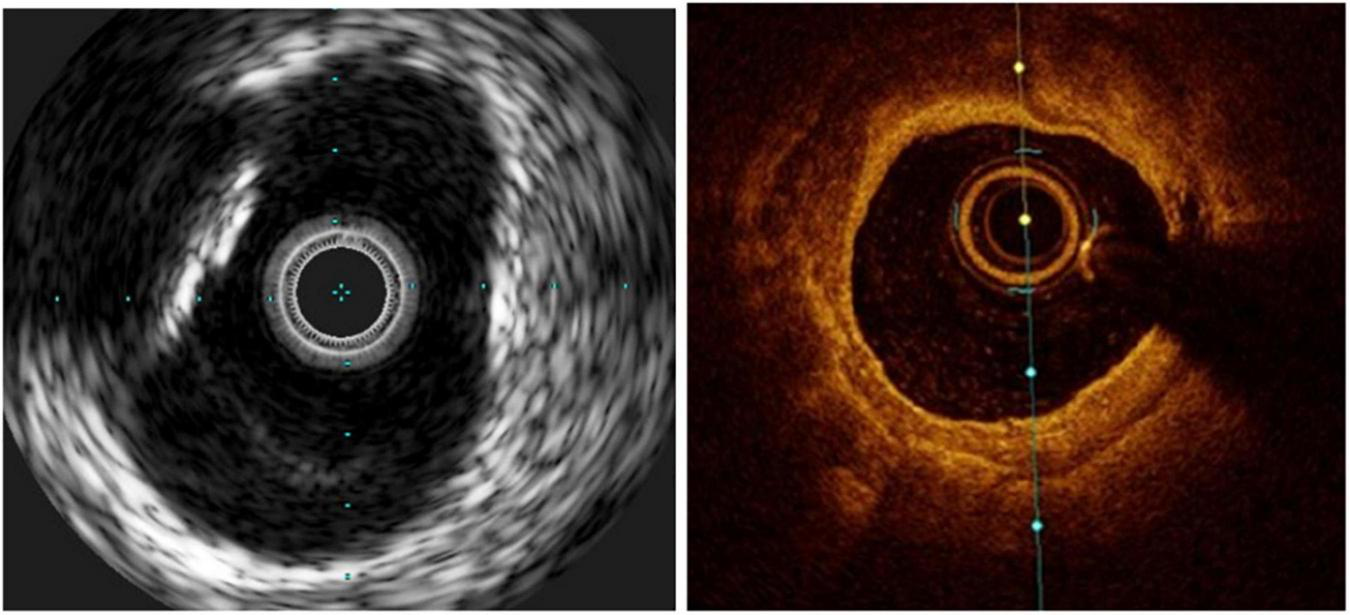

The most frequent technically preventable mechanism of ISR in the DES era is stent underexpansion (40), often unrecognized at angiography (Figure 2). Post-PCI minimum stent area (MSA) is consistently the strongest predictor of ISR. In an early study of almost 500 lesions in 425 patients who underwent successful IVUS-guided stenting, based on the empiric criteria, an intrastent minimal lumen cross-sectional area ≥55% of the average reference vessel was the only criterion that was associated with a higher probability of freedom from ISR, independently from vessel size (41). However, more recent accumulating evidence suggested that the absolute stent expansion (MSA as an absolute measure) matters more than the relative expansion (MSA compared to a predefined reference area) in predicting the stent patency in the long term. In a study of over 1,500 patients [nearly 1,100 with paclitaxel-eluting stents (PESs), and nearly 500 with BMS], post-PCI MSA was the independent predictor of subsequent ISR at 9 months, with an optimal threshold of 5.7 mm2 for PES (42). Similarly, for sirolimus-eluting stents (SESs), post-procedural final MSA by IVUS was one of the only two independent predictors of angiographic restenosis; the other predictor being the stent length. In that study, the final MSA cutoff that best predicted ISR was 5.5 mm2 (43). Similar data have been shown for the second-generation DES, where a study of almost 1,000 lesions identified the post-stenting MSA as the only independent predictor of angiographic ISR in zotarolimus-eluting stents (ZESs) and in everolimus-eluting stents (EESs). The best MSA cutoff value was 5.5 mm2 for the prediction of SES restenosis, 5.3 mm2 for ZES ISR, and 5.4 mm2 for EES (44). Most recently, this was challenged by an IVUS substudy of the ADAPT-DES registry (Assessment of Dual Antiplatelet Therapy with Drug-Eluting Stents), where ten different stent expansion indices were compared for their association with a primary endpoint of lesion-specific 2-year clinically driven TLR or definite stent thrombosis. Interestingly, only MSA/vessel area at the MSA site (best cutoff was 38.9%) was independently associated with the study endpoint, after adjusting for morphologic and procedural parameters. In other words, stent/vessel area at the MSA site was superior to absolute MSA (and other expansion indices) in predicting the study endpoint, driven mainly by the difference in TLR rather than stent thrombosis (45).

FIGURE 2

Stent underexpansion. OCT image of an incomplete expansion of a stent resulting in restenosis despite moderate neointima proliferation. The asterisks (*) mark stent struts. The small picture demonstrates the incomplete apposition at angiography.

Concurring with the intravascular ultrasound (IVUS) findings, post-stenting optical coherence tomography (OCT) has shown that a small MSA (defined as <5.0 mm2 for DES) is an independent predictor of 1-year device-oriented clinical endpoints (49). It is important to note, however, that these thresholds do not define optimal stenting, such that a larger MSA is still associated with less ISR, until an MSA of about 8 mm2, where a plateau is reached (50).